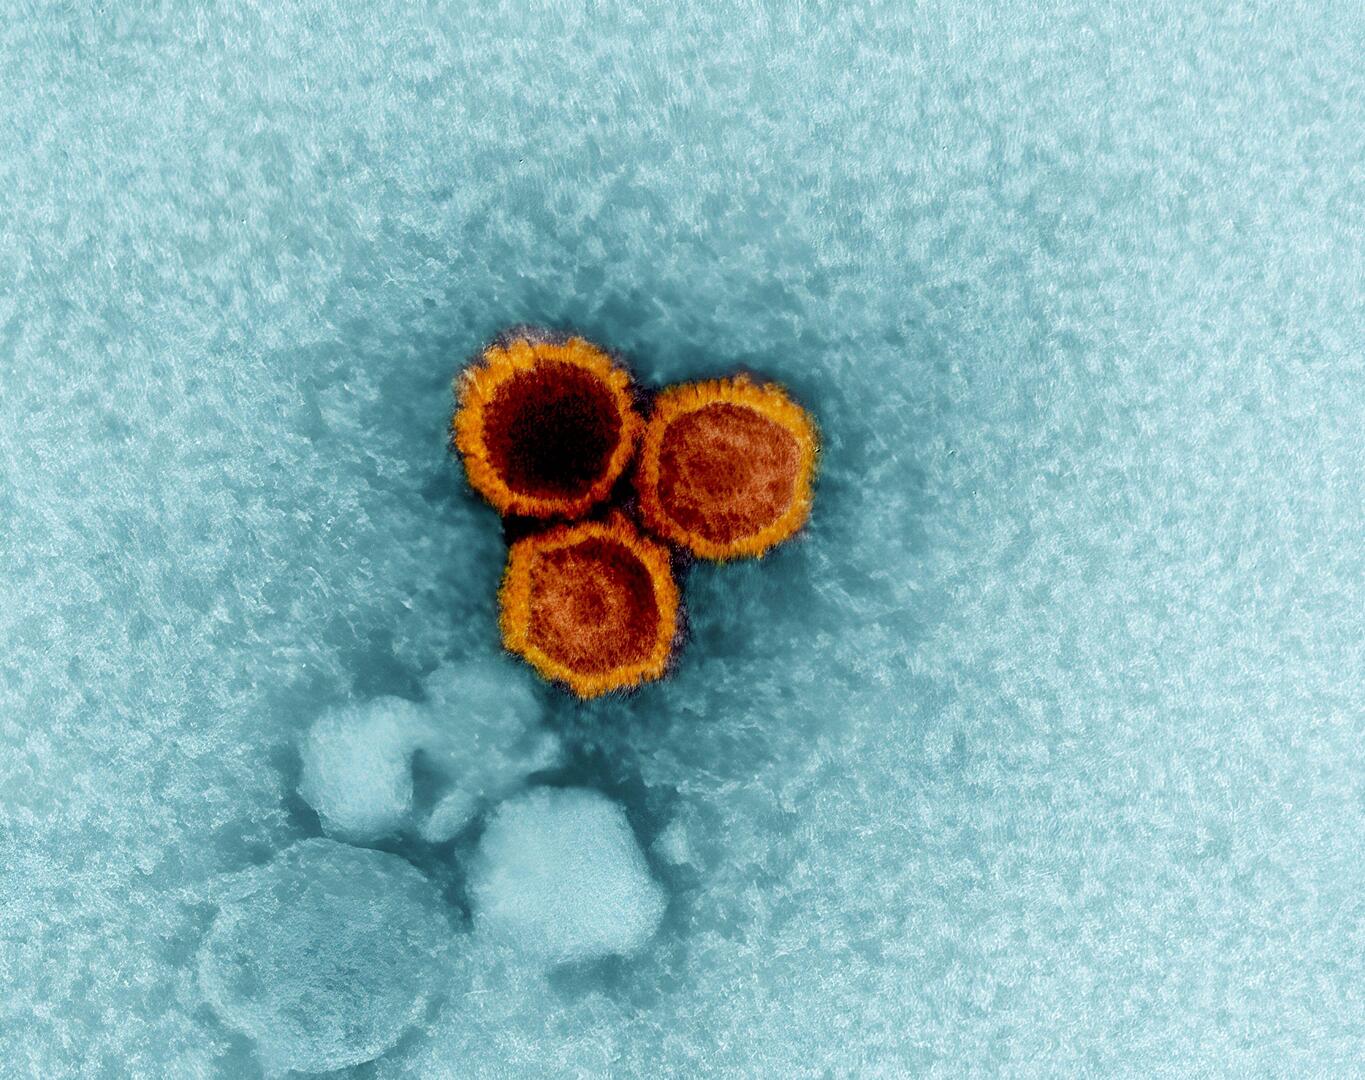

علاقة مقلقة بين نوع مياه الشرب وزيادة خطر مرض عصبي مزمن

أظهرت دراسة حديثة أن نوع مياه الشرب التي يتناولها الإنسان قد يكون له علاقة بزيادة خطر الإصابة بمرض باركنسون.

ويعرف مرض باركنسون بأنه اضطراب عصبي مزمن يسبب الرعاش وصعوبة في الحركة والتوازن وتيبس العضلات ومشاكل في الكلام، وتتفاقم أعراضه مع مرور الوقت.

وفي الدراسة، ركز باحثون من مدينة نيويورك وأريزونا على تحليل تأثير مصادر المياه الجوفية على هذا المرض.

ودرس الفريق أكثر من 12 ألف شخص مصاب بباركنسون، وأكثر من مليون شخص غير مصابين، جميعهم يعيشون بالقرب من مواقع أخذ عينات المياه الجوفية لمراقبة جودتها.

وأظهرت النتائج أن الأشخاص الذين يحصلون على مياههم من مواقع المياه الجوفية الحديثة — أي التي أُنشئت خلال الـ 75 عاما الماضية — كانوا أكثر عرضة بنسبة 11% للإصابة بالمرض مقارنة بمن يحصلون على المياه من المصادر القديمة. كما تبين أن شرب المياه من طبقات المياه الجوفية الكربوناتية، وهي طبقات صخرية قابلة للذوبان تحمل المياه، يزيد من خطر الإصابة بنسبة تصل إلى 62% مقارنة بالمياه من الطبقات الجليدية.

ويعتقد الخبراء أن المياه الجوفية القديمة أكثر نقاء لأنها تأتي من أعماق أكبر، ما يحميها من الملوثات مثل المعادن الثقيلة والمبيدات الحشرية.

وتنتشر طبقات المياه الجوفية بشكل واسع في الولايات المتحدة، حيث تخدم نحو 145 مليون شخص، ويأتي حوالي نصف مياه الشرب في البلاد من هذه المصادر. ويُعتقد أن طبقات المياه الجوفية الجليدية، التي تشكلت أثناء العصر الجليدي، تعمل كمرشح طبيعي بفضل تكوينها من الرمل والحصى، ما يقلل من تلوث المياه.

وأكدت بريتاني كرزيزانوفسكي، معدة الدراسة والباحثة في معهد أتريا للأبحاث في نيويورك، أن "إحدى طرق دراسة التعرض للتلوث الحديث هي من خلال مياه الشرب. المياه الجوفية الحديثة، الناتجة عن أمطار السبعين إلى الخمسة والسبعين عاما الماضية، تتعرض لمزيد من الملوثات، بينما المياه القديمة تبقى أنظف إذا كانت محمية بعمق. وجدت دراستنا أن عمر المياه الجوفية وموقعها يعدّان من عوامل الخطر البيئية المحتملة لمرض باركنسون".

ولفتت الدراسة إلى أن نحو 3463 من المصابين بمرض باركنسون يحصلون على مياه الشرب من طبقات المياه الجوفية الكربوناتية، و515 من طبقات المياه الجوفية الجليدية، و8329 من طبقات مياه جوفية أخرى. بينما بين غير المصابين، حصل 300264 على المياه الكربوناتية، و62917 على المياه الجليدية، و860993 على مصادر أخرى.

وحذر الباحثون من أن الدراسة لا تثبت أن المياه الحديثة تسبب باركنسون، لكنها تشير إلى وجود ارتباط محتمل بين نوع الماء وخطر الإصابة، خاصة عند التعرض الطويل للمياه الجوفية الحديثة والملوثة. ويُنصح بغلي المياه أو استخدام فلاتر منزلية للحد من الملوثات.